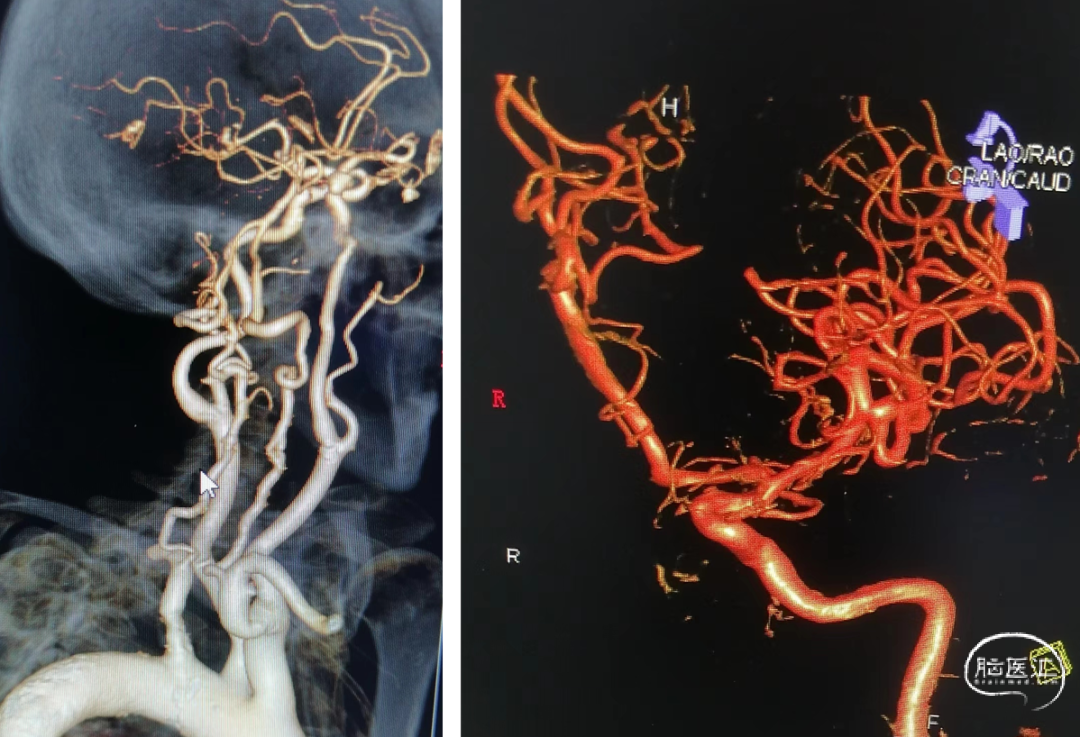

术前影像学检查:CTA示右侧颈内动脉后交通段动脉瘤。

术前DSA造影:通过3D工作位测量动脉瘤大小约6.32mm*9.57mm,瘤颈宽约5.61mm,载瘤血管直径:近端直径3.85mm,远端直径3.62mm。

右侧颈内动脉后交通段宽颈动脉瘤。